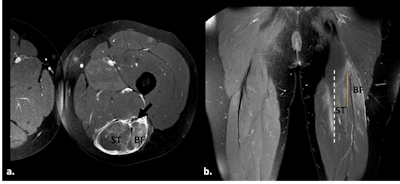

BAMIC 3b injury. Fat-suppressed proton-density weighted axial (a) and coronal images (b) show muscle edema >15 cm (white dotted line) at the myotendinous/intramuscular tendon, with tendon distortion >5 cm (orange dotted line) with a wavy appearance. Interfascial hematoma and surrounding the ischiatic nerve (black arrow). Semitendinous (ST), biceps femoris (BF).